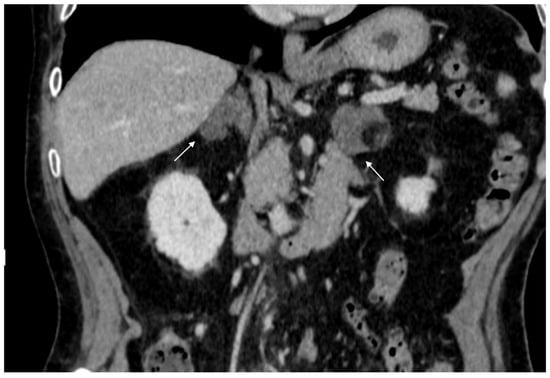

74-year-old male patient. Following an MRI of the digestive tract incidental finding of bilateral adrenal secondary hyperplasia. Both enlarged limbs adrenal glands > 10 mm thick with multiple nodularity hypodense on non-contrast CT (arrows).

The most common malignant adrenal lesions are metastases, typically originating from lung, breast, stomach, liver, kidney, pancreas, and colon cancers, as well as melanomas and malignant lymphomas (Figure 3) [20]. Alternatively, primary adrenal diseases such as pheochromocytomas or adrenocortical carcinomas (ACC) may be present (Figure 4) [9]. ACC is a rare and aggressive malignant tumor of the adrenal cortex, with a poor prognosis and an incidence of approximately one case per million people per year. The most common clinical manifestation of ACC is cortisol overproduction, observed in up to 40% of cases [21]. Pheochromocytomas are rare, typically benign tumors (90%), though a small percentage may be malignant [22,23]. They are associated with catecholamine production and are evaluated by measuring metanephrine and normetanephrine levels [1,24]. Less common malignant adrenal lesions include lymphomas and neuroblastomas, one of the most common abdominal tumors in children [7,25,26].